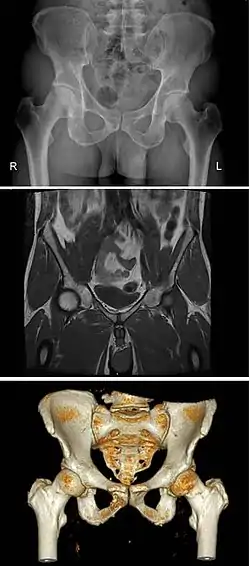

The same human pelvis, front imaged by x-ray (top), magnetic resonance imaging (middle), and 3-dimensional computed tomography (bottom)